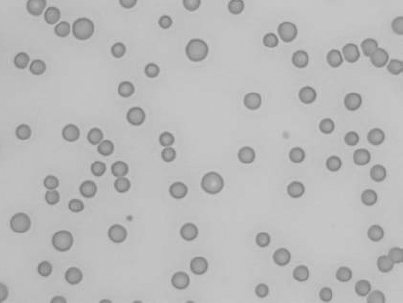

See Figs 1.3–1.24 for pictures of various types of RBC morphology.

Figure 1.11 Canine blood film showing echinocytes III (also see color section).

Figure 1.12 Feline blood film showing echinoelliptocytes (also see color section).